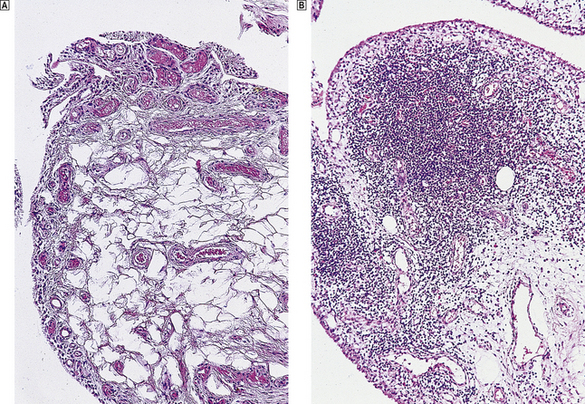

Osteosarcoma

This aggressive malignant tumour usually affects adolescents and most often involves the distal femur, proximal tibia or humerus (Fig. 25.13). Occasional cases occur in the elderly, usually complicating Paget's disease or previous radiation. Other cases are associated with familial cancer syndromes, notably the retinoblastoma syndrome and the Li–Fraumeni syndrome. Somatic mutations of the tumour suppressor genes that have germline mutations in these syndromes (RB1 and p53) are common in sporadic osteosarcomas. These tumours grow rapidly and often have a typical X-ray appearance. Osteosarcomas are characterised histologically by pleomorphic and mitotically active osteoblasts associated with osteoid; some variants are exceedingly vascular. Approximately 50% of patients can now be cured by a combination of surgery and intensive chemotherapy. Although amputation was previously necessary, local resection and the insertion of prosthetic joints is now usually possible.

image

Fig. 25.13 Osteosarcoma. The cut surface of a rapidly growing tumour in the distal femur of a teenager.

Chondrosarcomas, in contrast to osteosarcomas, grow slowly and arise not only in long bones but also in the pelvis, ribs and spine (Fig. 25.14). These tumours may be well differentiated and can resemble normal cartilage. Surgical excision is the treatment of choice, as radiotherapy and chemotherapy are usually ineffective.

Fig. 25.14 Chondrosarcoma. The tumour has arisen in a pelvic bone of a 42-year-old female. Histologically the abnormal cartilage is much more cellular than normal.